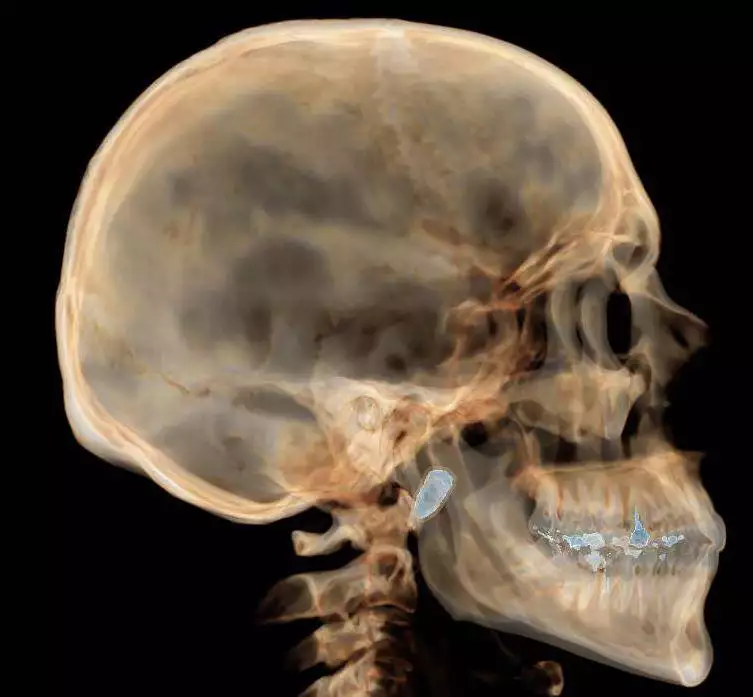

A 39-year-old IDF reservist, wounded in an extraordinary manner during an operation in the Balata refugee camp, is currently hospitalized at Beilinson Hospital, where doctors face a unique medical dilemma. The soldier, shot in the face by a terrorist, survived a near-fatal injury when a 2 cm-long, 1 cm-wide bullet entered through his nose and lodged behind his upper wisdom tooth.

Described as a “miracle” survival, the bullet’s trajectory was mere millimeters from a lethal outcome, marking the injury as exceptionally rare. The case has sparked intense debate among Beilinson’s medical team, led by Prof. Gabriel Chaushu, head of the Oral and Maxillofacial Surgery Department, over whether to surgically remove the bullet or leave it permanently in place, weighing the soldier’s pain against the risks of a complex procedure.

The reservist reports significant pain and difficulty swallowing, yet the potential dangers of surgery are substantial. Prof. Chaushu explained, “The consideration of whether to remove the bullet or not is the benefit versus the risk of surgery. Surgery adds another scar and trauma and could lead to infections and risks. There is concern about several things: damage to a motor nerve that could cause facial paralysis (facial nerve), damage to blood vessels, damage to the nerve responsible for sensation in the lower jaw and tongue movement.” After multiple expert consultations during the soldier’s hospitalization and rehabilitation, the team noted significant improvement in jaw mobility through physiotherapy, leading to a decision to avoid surgery despite the ongoing pain.